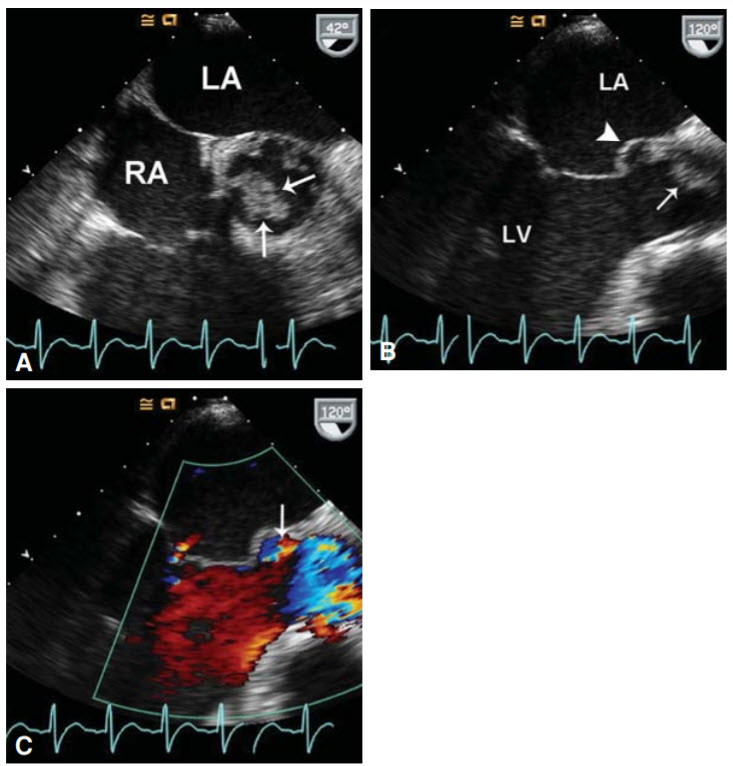

An echocardiogram shows the following figure:

Coxiella burnetii. This bacterial species is responsible for Q fever, a zoonotic infection that can be asymptomatic or cause pneumonia, hepatitis, and/or endocarditis. This patient has hepatitis and endocarditis, the latter of which should raise suspicion for Q fever given his history of recent tick exposure. Treatment is with doxycycline. Borrelia, Ehrlichia, Francisella, Babesia, and Rickettsia are all associated with ticks; however, they are less likely to be associated with hepatitis and endocarditis.